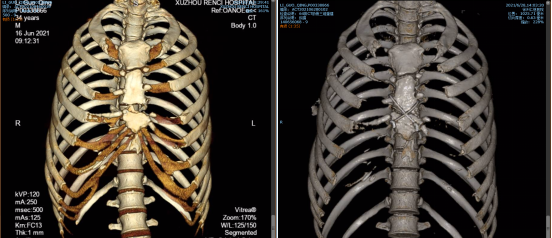

王保毅主任的手术团队为李师傅进行了“开胸探查+心包开窗术+胸骨骨折内固定+肋骨骨折内固定”的手术,术中首先清除心包内的积气,然后针对胸骨和肋骨骨折进行内固定。

术前术后胸骨对比图